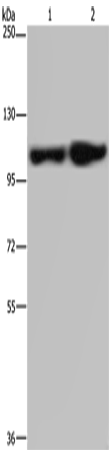

WB Predicted band size:

113 kDa

WB Positive control:

Human fetal liver and placenta tissue

WB Recommended dilution:

200-1000